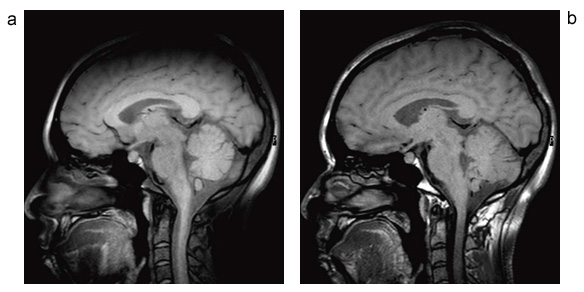

図5に,MSDE法とiMSDE法で撮像した頭部画像の比較を示す。MSDE法で目立っている頭頂部位の信号低下が,iMSDE法で改善していることがわかる。また,iMSDE法を用いた応用例を図6に示す。これは脳転移を確認するための検査で,造影後に撮像されている。図6 aは,3D-TSE法で撮像したT1強調像である。病変部位(▲)と血液信号(↑)が,ともに高信号として描出されており,病変部位の見極めを困難にする可能性がある。図6 bは,3D-MSDE-TSEで撮像した画像である。血液信号の抑制によって,病変部位のみを高信号として描出するため,検出能力の向上が期待できる。

図5 MSDE法とiMSDE法で撮像した頭部画像

MSDE法(a)では頭頂部の信号低下が目立つが,iMSDE法(b)によってそれが明らかに改善されていることがわかる。

(画像ご提供:山形大学様)